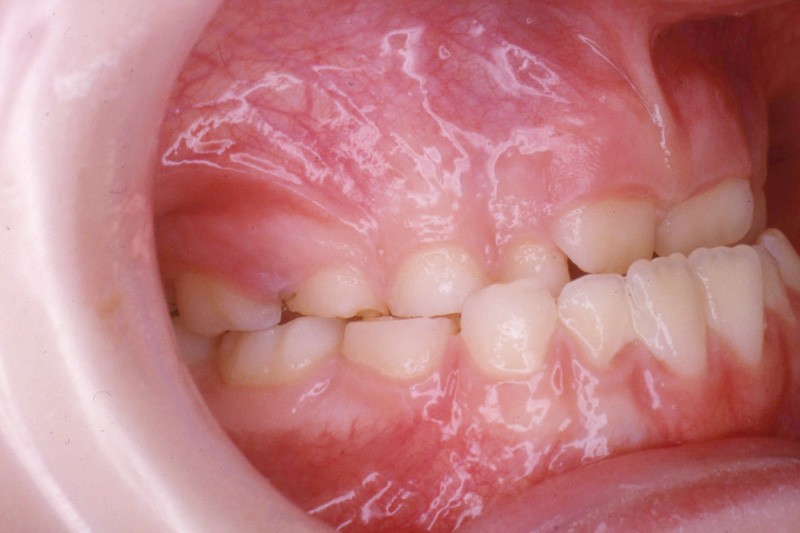

L’examen de la denture (fig. 3 à 5) montre :

• dans le sens antéro-postérieur, des relations molaires et canines de type classe III d’Angle et une inversion des rapports incisifs,

• dans le sens transversal, une endomaxillie bilatérale prédominante dans la région canine.